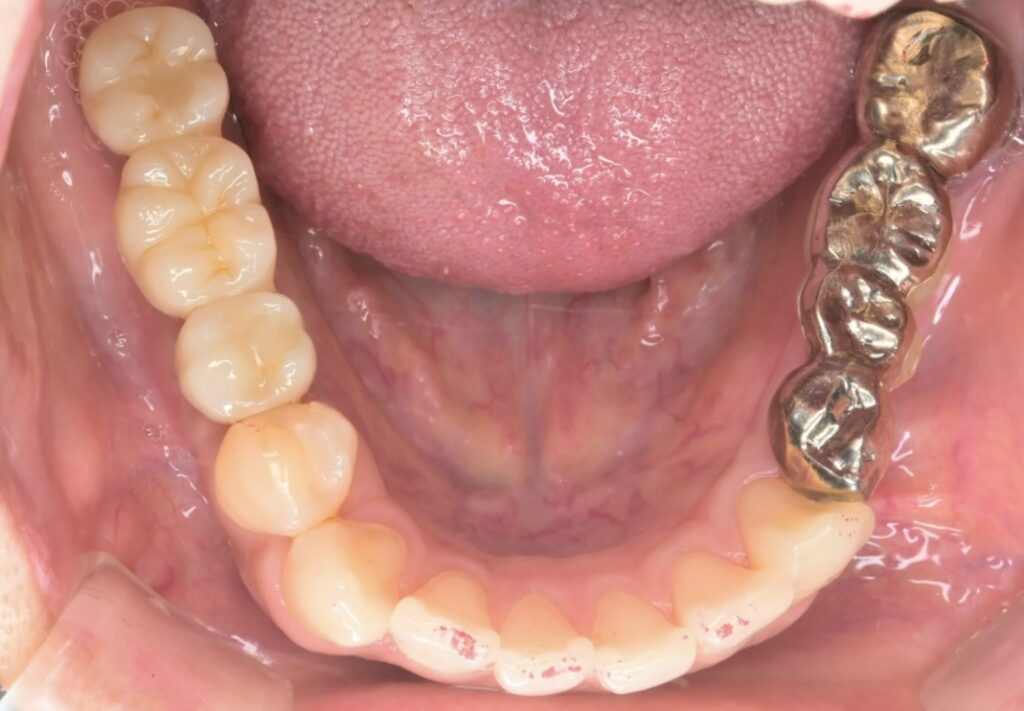

症例写真

(右下の奥歯が欠損している状態)

口腔内の状況